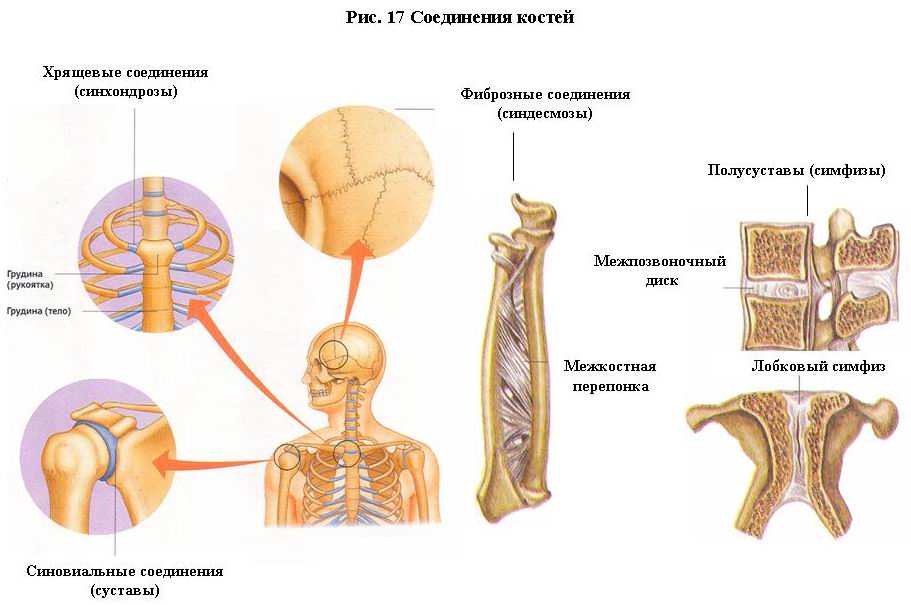

Структура и анатомия синдесмоза: научные иллюстрации